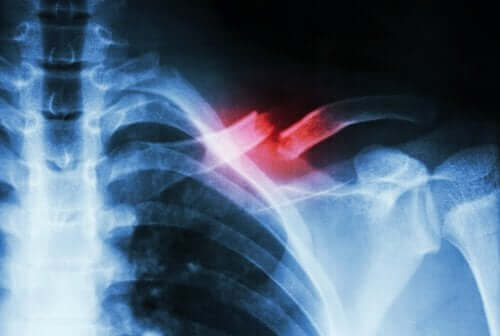

Стресовата фрактура е вид счупване или пукнатина в костта. Тези фрактури се случват поради многократна микротравма или претоварване, както казахме по-горе. В допълнение, те могат да представят силна болка при извършване на определени физически дейности. Тогава, тези фрактури често изчезват, когато дейностите приключат.

Може да не го знаете, но костите са изградени от колаген. Това е съединение, което улеснява процеса на костно ремоделиране, когато е костта е подложена на напрежение. Това е начин да се реабсорбира всяка повредена тъкан и след това да се образува отново. Ако обаче въздействието е непрекъснато или прекалено внезапно поради претоварване, фрактурата надвишава способността на тялото да попълва колагена. Точно това се случва, когато има стресова фрактура, поради претоварване или повтарящи се движения или остеопороза.